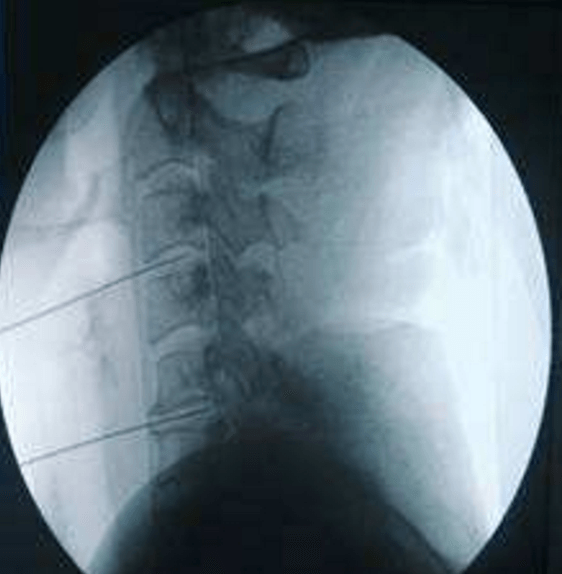

頸、腰椎間盤射頻微創(chuàng)手術(shù)

經(jīng)過多年的發(fā)展,現(xiàn)在的延安大學(xué)咸陽醫(yī)院疼痛科在診療技術(shù)上已經(jīng)達到一流的水平。尤其在頸、腰椎間盤突出微創(chuàng)治療方面,手術(shù)量居地區(qū)前列,脊柱壓縮骨折椎體成型術(shù)、頸、腰交感神經(jīng)射頻調(diào)控微創(chuàng)手術(shù)、三叉神經(jīng)痛、帶狀皰疹后神經(jīng)痛以及外周血管介入、腫瘤微創(chuàng)介入、內(nèi)臟出血等介入治療方面,為地區(qū)最優(yōu)秀的疼痛科之一。